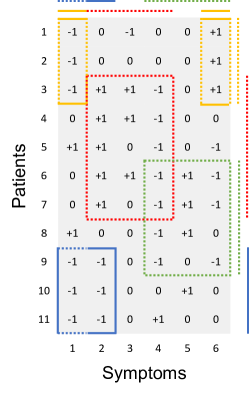

A simple example with 11 patients and 6 ternary symptoms is shown in Figure 2 for illustration. There are 4 diseases, each represented by one color (corresponding to the dashed blocks inside the matrix in Figure 2). Importantly, patients and symptoms can be linked to multiple diseases. For example, patient 9 has both, the blue and the green disease, and symptom 4 can be triggered by either the red or the green disease. Available prior information is incorporated in this example. For instance, if patients 9, 10, 11 are diagnosed with the blue disease, they will be grouped together deterministically (represented by the blue solid line on the side). Likewise, if the yellow disease is known to lead to symptoms 1 and 6, we fix them in the model (represented by the yellow solid lines on the top).

The proposed DFA is closely related to matrix factorization and random networks. We briefly discuss two alternative interpretations of DFA for the case of the observed data being ternary. Binary outcomes are a special case of ternary outcomes; generalization to more than three categories is straightforward. We use the same toy example as in Section 2.4 to illustrate the alternative interpretations.

where , , with element-wise multiplication , and . Figure 3 illustrates the factorization. The matrix describes the PD relationships. and characterize the SD relationships where and . The number of diseases is less than the number of patients and the number of symptoms.